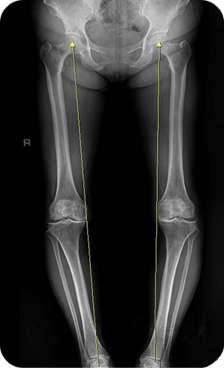

퇴행성 관절염은 대개 무릎의 내측 부위부터 시작되어 외측으로 진행되는데, 내측 부위에만 관절염이 발생한 60대 이하의 환자의 경우에는 근위 경골 절골술이 치료의 대안이 될 수 있습니다. 무릎 내측에 관절염이 발생하면 무릎은 내반(O자 다리)변형이 생깁니다.

정상 무릎은 체중이 무릎의 중앙을 통과해서 발목으로 전달이 되는데, 무릎이 내반되면 체중이 무릎의 내측으로 전달되어 이미 손상된 내측 부위로 과도한 체중이 부하되고 퇴행성 관절염이 급속히 악화된다.

HTO는 60대 이전에 무릎 안쪽에만 관절염이 발생해있고 내반 변형이 생긴 환자에서 시행합니다. 모든 환자에서 수술이 가능한 것은 아니고 무릎이 과도하게 내반된 경우, 무릎이 90도 이상 안 구부러지거나, 무릎이 15도 이상 안 펴지는 경우 과도한 비만 등의 경우는 수술이 불가능 합니다.

먼저 HTO 수술 전에 관절경을 시행해서 무릎 외측 부위에 있는 연골 상태의 정상 유무를 확인하고 정상인 경우에 HTO 수술을 진행한다.

수술 방법은 종아리뼈(경골) 상단에서 아랫쪽으로 약 5,6cm 되는 부위를 절골한 후 뼈를 벌려서 쐐기 모양의 빈 공간을 만들면 무릎의 내반 변형이 교정이 되는데, 이때 좀 더 과하게 교정을 해서 무릎의 바깥 부분으로 체중이 부하되도록 한다.

이 상태에서 금속판을 이용해서 교정된 뼈를 고정하고, 쐐기 모양의 빈 공간은 뼈 이식을 통해서 결손을 채운다. 이렇게 HTO 수술을 하면 수술 후에, 연골이 망가진 내측으로 체중이 전달되지 않고 외측에 있는 정상 연골로 체중이 전달되기 때문에 무릎의 통증이 감소된다.